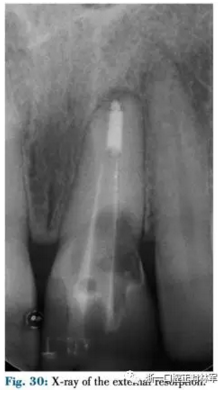

患者為一名41歲女性,由于創(chuàng)傷及外吸收導(dǎo)致左上中切牙骨缺損(圖30-32)。骨缺損使種植修復(fù)變得復(fù)雜需要GBR技術(shù)(圖33),因此需要大量的軟組織覆蓋薄膜,采用正畸牽引實(shí)現(xiàn)。

為保證治療期間美觀效果患者選擇舌側(cè)矯治器。上頜全口粘接舌側(cè)托槽,21部分牽引,序列為0.016銅鎳鈦,0.016TMA,0017×0.017TMA(圖34-37)。第一階段為沿牙齒長(zhǎng)軸純牽引,隨后手術(shù)需要鄰間骨峰的存在以便種植時(shí)GBR及側(cè)切牙GTR術(shù)的開(kāi)展,因此首先將側(cè)切牙向遠(yuǎn)中傾斜過(guò)矯正近中峰,隨后向近中傾斜提升遠(yuǎn)中峰,通過(guò)GOBR引導(dǎo)骨再生。給予唇向轉(zhuǎn)矩將牙冠舌傾。牽引量不是由最終增加的硬組織決定的,而是由軟組織增量決定的。這也是牙周醫(yī)生的需求:通過(guò)引導(dǎo)正畸“軟組織”再生術(shù)獲得大量的軟組織允許將來(lái)的手術(shù)的進(jìn)行。